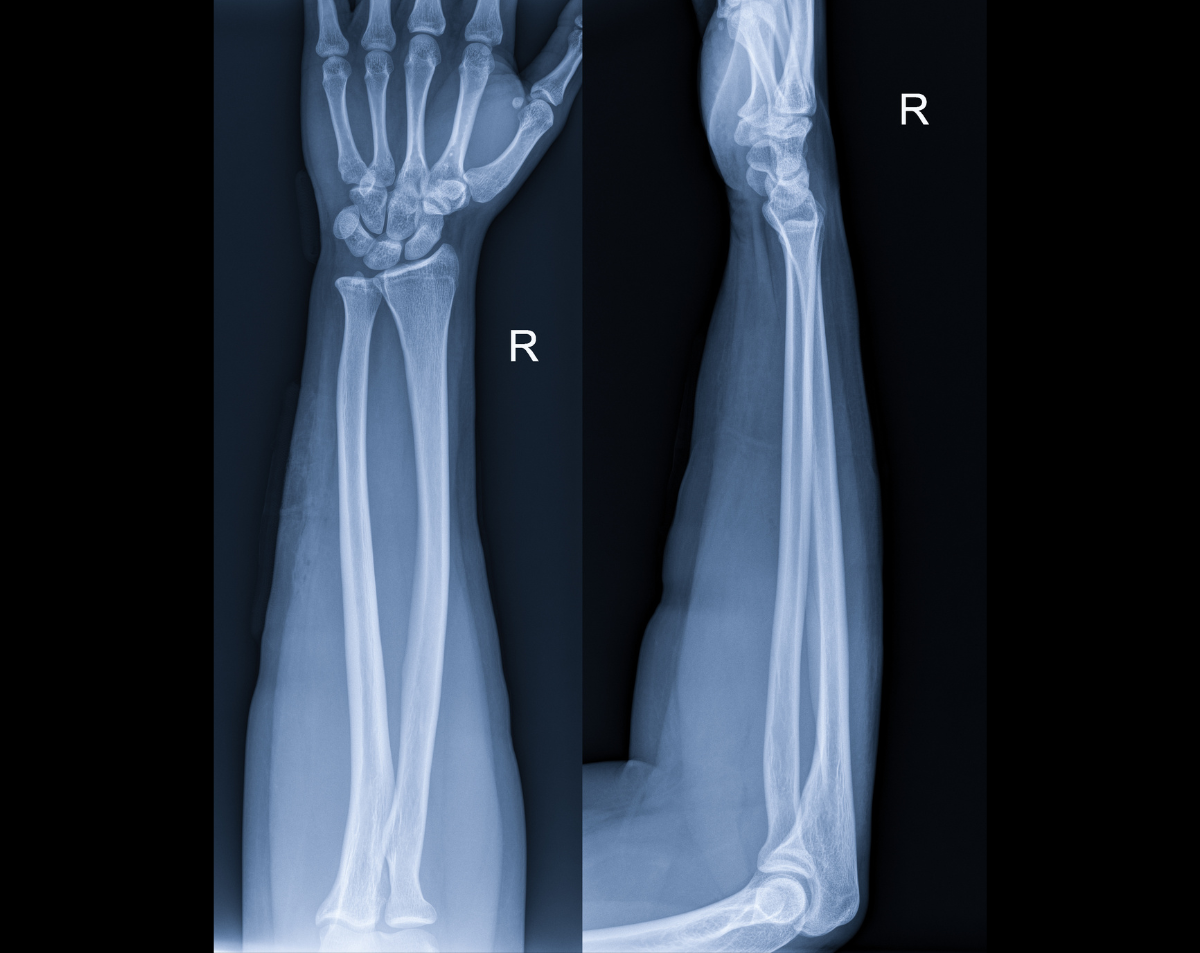

A right forearm X-ray provides detailed images of the radius and ulna—the two long bones that connect the wrist to the elbow. Physicians rely on this test to evaluate fractures, dislocations, infections, or other abnormalities. At Desert Mobile Medical, we bring hospital-grade digital X-ray technology directly to you, eliminating the need for urgent care or radiology center visits. You receive fast, precise diagnostics in the comfort and privacy of your home, office, or care facility.